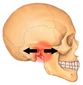

Çeneyi Nasıl İleri Alabilirim?Çene yapısı, yüz estetiği ve fonksiyonu açısından önemli bir rol oynamaktadır. Çenenin ileri ya da geri pozisyonu, yüz simetrisi, diş sağlığı ve genel estetik algı üzerinde belirleyici etkilere sahiptir. Bu makalede, çenenin nasıl ileri alınabileceği üzerine çeşitli yöntemler ve teknikler ele alınacaktır. 1. Ortodontik Tedavi YöntemleriOrtodontik tedavi, dişlerin ve çenenin düzgün bir şekilde hizalanmasını sağlamak amacıyla kullanılan bir yöntemdir. Çenenin ileri alınmasında aşağıdaki ortodontik yaklaşımlar etkili olabilir:

2. Cerrahi YöntemlerÇenenin yapısal bir problemi varsa, cerrahi müdahale gerekebilir. Aşağıdaki cerrahi yöntemler çenenin ileri alınmasında kullanılabilir: